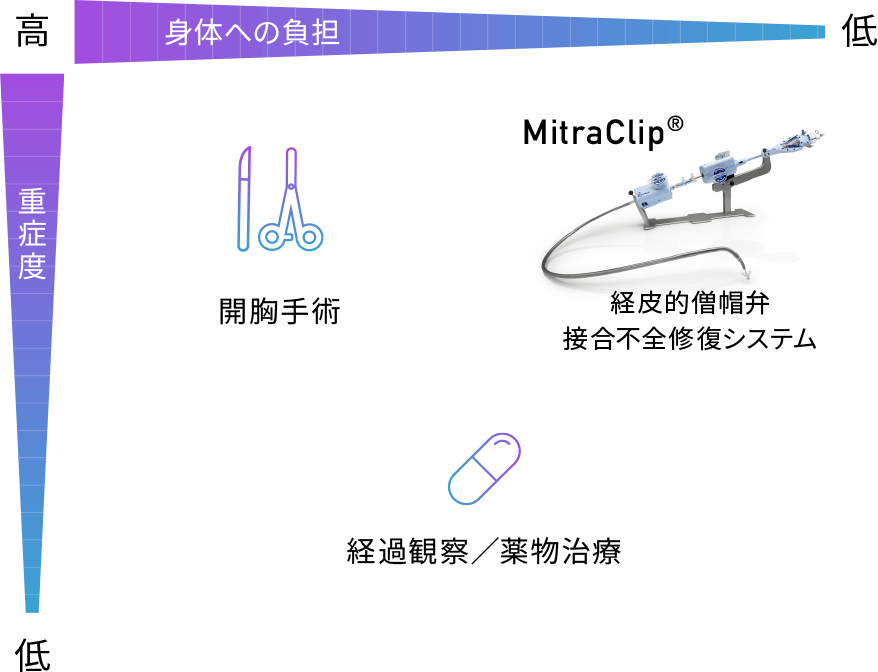

僧帽弁閉鎖不全症とは

心不全の原因ともなる、血液が逆流してしまう心不全の一つです

心臓は主に4つの部屋に分かれています。それぞれの部屋には、血液が逆流しないように、合計4つの扉(弁)がついています。肺で酸素化された血液は、まず左心房に集められ、次に全身へ血液を送り出すポンプ=左心室に充填されます。これら左心房、左心室の間に存在するのが、僧帽弁です。僧帽弁逆流症の多くは、弁と左心室の間を結ぶひも(腱索)が一部切れたり、左心室自体が大きくなることで弁がひっぱられたり、僧帽弁のわくが拡大することで、うまく弁が閉じることができなくなり、血液が左心室から左心房へ逆流してしまうことで生じます。

僧帽弁閉鎖不全症の僧帽弁

僧帽弁閉鎖不全症には大きく分けて2つのタイプ、「器質性(一次性)MR」「機能性(二次性)MR」があります。

器質性(一次性)MR

僧帽弁の左心室側にある腱索(僧帽弁と左心室を結ぶひも)が何らかの原因で切れたり、伸びたりすることで、僧帽弁自体の合わさりが悪くなり(接合不全)、血液が左心房へ逆流する状態です。

機能性(二次性)MR

心筋梗塞などの虚血性心臓病、拡張型心筋症などにより左心室の動きが悪くなったり、心臓自体が拡大することで、僧帽弁を結ぶひも(腱索)がひっぱられたり、僧帽弁のわくが大きくなることで、僧帽弁自体の合わさりが悪くなり(接合不全)、血液が左心房へ逆流する状態です。